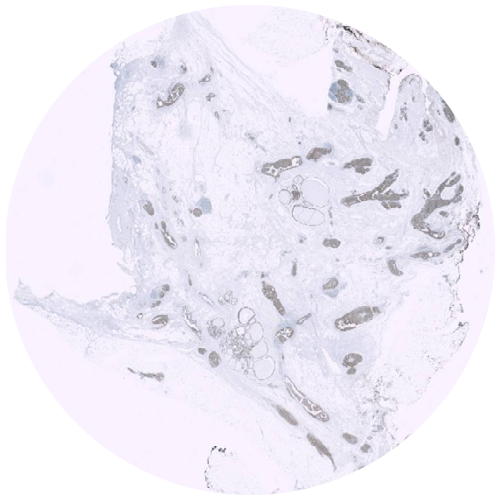

Physical IHC

ViewsML uses deep learning to eliminate physical staining, delivering virtual results in seconds at a fraction of the cost, all the while fitting into existing workflows.

Virtual IHC